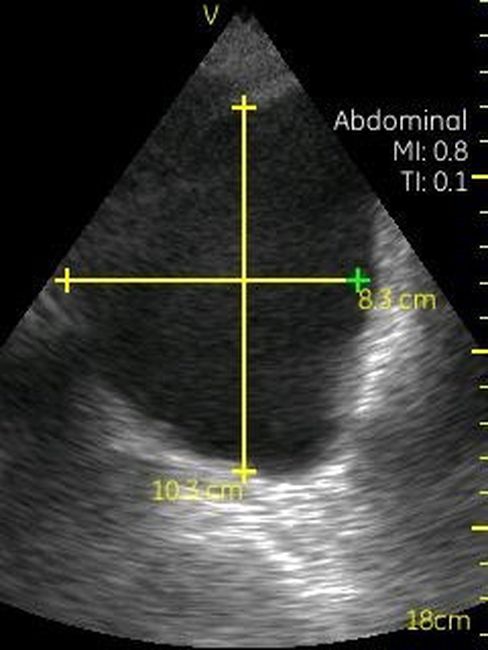

GE VSCAN – это УЗИ аппарат, реализованный в ультракомпактном корпусе, позволяющий делать черно-белые изображения тканей и органов реального времени. Ключевым отличием данного прибора от других моделей GE является его карманный размер, он чуть больше обычного смартфона. Идеальное средство для бригад скорой помощи, врача, принимающего пациента на дому, экстренной диагностики в полевых условиях.

Невозможно было представить раньше, что УЗИ аппарат может помещаться на ладони руки человека. Теперь это реальность, воплощенная в корпусе и технологической начинке GE VSCAN. Инженеры заложили возможность получения дополнительной визуализации кровотока с цветной кодировкой в режиме реального времени для полноценной постановки диагноза на месте.

Визуализация Vscan:

· Черно-белый режим для визуализации анатомических структур в реальном времени.

· Наложение кровотока с цветовой кодировкой в реальном времени.

· Поле зрения в черно-белом режиме: до 75 градусов с максимальной глубиной 25 см.

· Сектор цветного режима показывает кровоток с углом обзора 30 градусов

· Широкополосный фазированный датчик с частотой от 1,7 до 3,8 МГц.